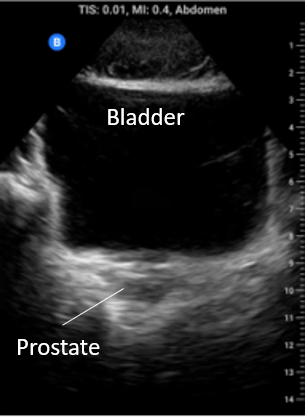

Pelvis: In the midline below the abdominal fold but superior to the pubic symphisis begin with the probe in transverse. Fan posterior to anterior through the bladder. In males pay particular attention to the rectovesical pouch and in females to the rectovaginal space (pouch of Douglas). Also look at the bladder edges for angular anechoic regions indicating fluid settling around the bladder and bowel.